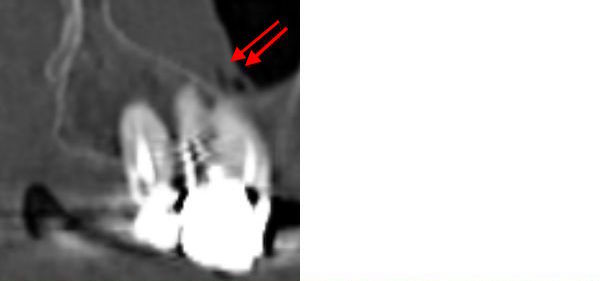

73-jährige Patientin (25.06.2021 / 404)

Das DVT zeigt, dass die Kieferhöhlenschleimhaut über den zwei verdächtigen Molaren stark angeschwollen ist. Zudem befinden sich in der Schwellung genau über den beiden wurzelbehandelten Molaren zwei kleine rundliche Aufhellungen. Das könnten Mikroabszesse sein, die von Bakterien in den Wurzelspitzen verursacht werden.

Aber erst die zwei kleinen Mikroabszesse in der Schleimhaut (rote Pfeile) konnten

die Patientin motivieren, den 16 zu extrahieren.